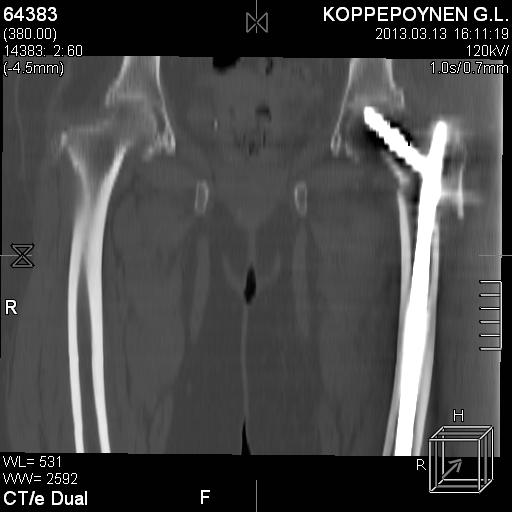

[Ortho] Чрезподвертельный перелом бедра. Остеосинтез стержнем. Перелом металлофиксатора. Дальнейшая тактика?

Делали КТ после операции.